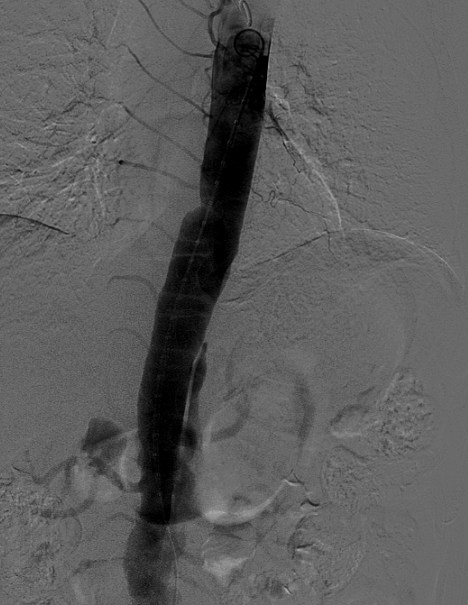

心急的家人经过四处打听,在朋友介绍下,沐叔来到了广东省第二人民医院,找到心血管外科主任、主任医师钟志敏。钟志敏主任团队在了解沐叔情况后,立即安排详细的主动脉CTA检查和主动脉造影检查明确沐叔主动脉夹层自降主动脉撕裂到双侧髂动脉,且部分连接到重要脏器的血管分支也受到累及,随时存在破裂的危险。

▲胸腹主动脉夹层CTA

“根据沐叔的主动脉夹层起始部位,首选治疗方式是经血管介入主动脉覆膜支架腔内隔绝手术,即在降主动脉置入覆膜支架,达到封闭主动脉内膜破口,达到血管腔重新塑型的目的,但是经过主动脉造影检查发现,沐叔的胸降主动脉段假腔已经塑型,将真血管腔挤压成头发丝那样细小,真腔血管壁还有出现黏连,连极细小的引导导丝都没办法通过真血管腔,而且勉强通过导丝会引起患者剧烈疼痛,甚至可能引起腹腔脏器缺血改变、血管破裂大出血,危及生命,介入手术操作变得相当棘手”钟志敏主任说。